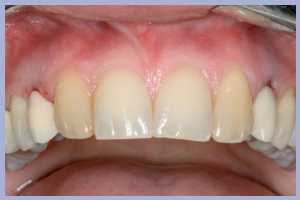

La valutazione clinica al momento della consegna dei manufatti e clinico-radiologica a 3 mesi dalla consegna manifestava una completa integrazione tissutale con eccellente recupero estetico e funzionale (Figg. 29-30).

- Figg. 29a, b Manufatti di destra e radiografia di controllo. Si noti l’ottima integrazione tissutale

- Figg. 30a, b – Manufatti di sinistra e radiografia di controllo